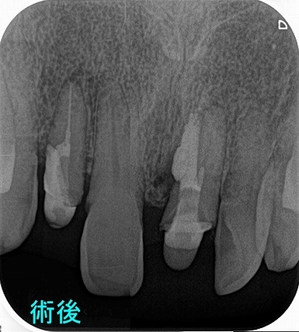

術後

右上2:破折片を抜いてレジンにて立ち上げ

左上1:パフォレーション部をMTAセメントにてリペア